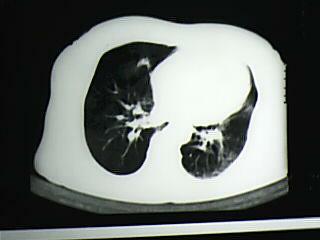

以下是引用bmw011在2009-4-14 19:14:00的发言:[br]右肺继发型肺结核---纵隔淋巴结多发钙化----左肺支扩。支持

以下是引用杀毒软件在2009-4-14 17:52:00的发言:[br]考虑---右肺继发型肺结核---纵隔淋巴结多发钙化----左肺支扩

以下是引用黑白光影在2009-4-14 20:36:00的发言:[br]右肺继发型肺结核;左下慢性支气管炎性病变。